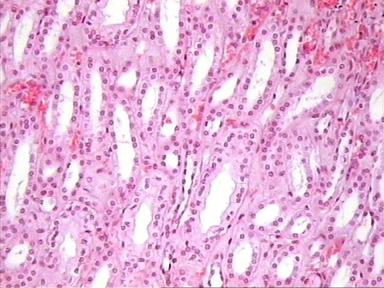

Médula renal